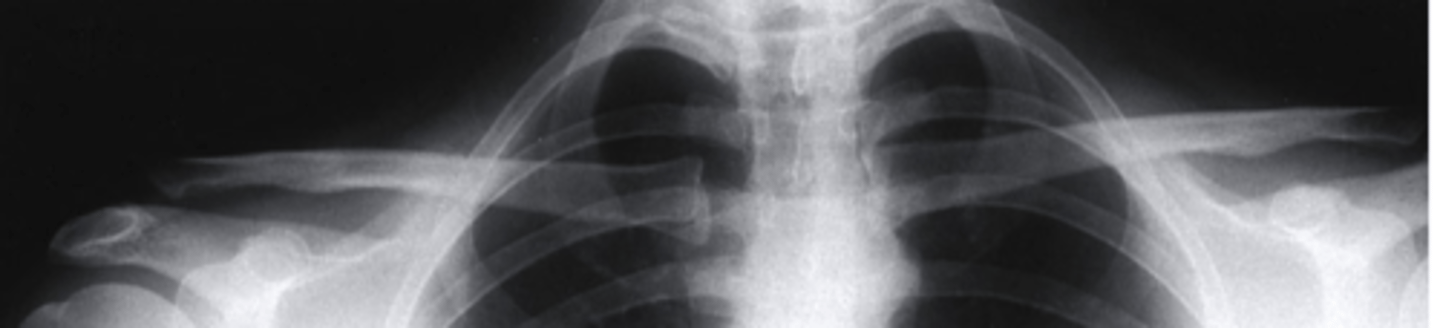

WB

Based on this photo, is this person WB or NWB?